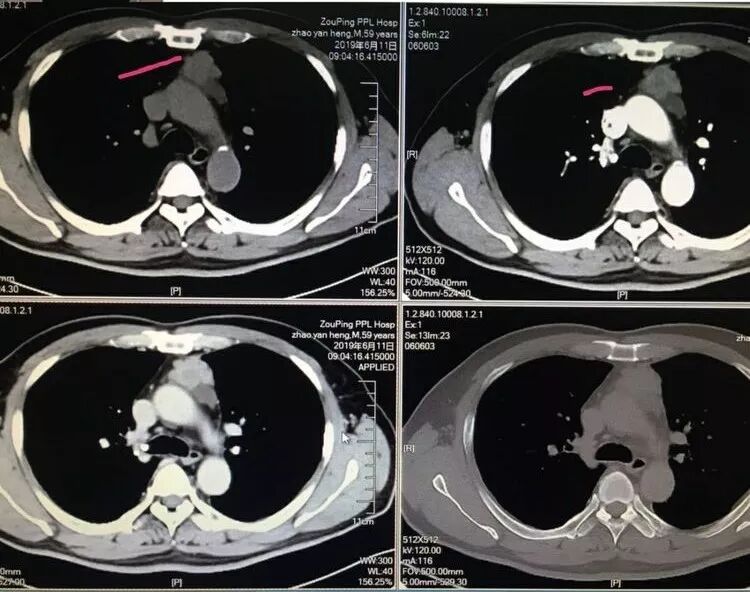

男性,中年,前上纵隔肿瘤,边界清晰,不光滑,强化不均匀,随访增大,淋巴结增大,考虑胸腺瘤,倾向侵袭性可能鉴别淋巴瘤?

中年男性,前纵隔占位,分叶状,两次比较,病灶增大,增强扫描中度强化,周围淋巴结,考虑恶性,胸腺癌可能性大。淋巴瘤待排

中年男性,前纵膈软组织结节,前后一年复查病灶明显增大,边缘不规则,周围脂肪间隙模糊,增强后明显不均匀强化,周围可见低密度,病灶生长迅速,首先考虑恶性肿瘤,胸腺癌可能大

中年男性,前纵隔占位,肿物不规则,有分叶,中度强化,考虑恶性,胸腺癌可能

小溪流:

红日东升:

男性,59岁,无肌无力。前纵隔占位,偏侧,形态不规则,边缘分叶状,似有点状微钙化,病灶较前4年前增大,明显强化,考虑恶性,周围似见小淋巴结,倾向胸腺癌。

前纵膈占位,逐渐进展,考虑恶性,应该是胸腺癌可能性大,鉴别诊断畸胎瘤

中年男性,前中纵隔不规则囊实性肿块,边缘有分叶,部分层面病灶周围脂肪间隙消失,增强扫描实性部分延迟强化,囊性部分不强化,临近见多个小结节影,考虑畸胎瘤,鉴于病灶四年明显增大,形态不规则,部分层面脂肪间隙消失,考虑恶变可能性大,鉴别胸腺癌

张小兵:

心灵鸡汤:

前纵隔团状影,形态不规则,有分叶,增强渐进性强化,与2015年对比有进展,纵隔主动脉旁淋巴结肿大,轻度强化,老年男性,考恶性肿瘤,侵袭性胸腺瘤?鉴别淋巴瘤?生殖细胞类肿瘤?实性畸胎瘤?建议穿刺活检。

中老年男性,前纵隔占位,形态不规则,分叶明显,局部脂肪间隙不清,增强明显强化,复查明显增大,邻近似见多个结节,心膈脚区似见结节。首先考虑胸腺癌,其次侵袭性胸腺瘤。

>40岁男性,前纵隔见一肿块,四年明显增大,分叶,上缘呈絮状改变,增强后不均匀性强化,可见未强化区,考虑恶性病变,胸腺癌,鉴别畸胎瘤(病灶内见点状高密度影,未强化区低密度影),

中年男性,前纵隔占位,边界清楚,可见分叶,增强后不均匀强化,内似有坏死,胸腺恶性肿瘤可能

中年男性,前纵膈占位,明显增大,分叶状,密度不均匀,增强明显强化,内见低密度区和分隔,有结节感,局部与邻近血管分界不清,周围可疑小淋巴结,两侧胸膜腔未见明显积液,首先考虑侵袭性胸腺瘤可能性大,代排胸腺癌。

晨读,中年男性,前纵膈软组织肿块,一年后复查病灶明显增大,边缘不规则,有分叶,有坏死,周围脂肪间隙模糊,增强不均匀强化,考虑恶性,胸腺癌,侵袭性胸腺瘤

中年人,前纵隔占位,边界不清,边缘可见分叶,与血管周围间隙模糊,一年多复查,肿块增大,未见明显淋巴结及周围器官转移,考虑恶性病变,侵袭性胸腺瘤,其次胸腺类癌。

中年男性 ,前纵隔肿块,分叶,局部边缘模糊,坏死。考虑侵袭性胸腺瘤或胸腺癌。

中年男性,前纵膈占位,分叶状,密度不均匀,增强呈明显强化,内见低密度区和分隔,局部与邻近血管分界不清,考虑侵袭性胸腺瘤。

中年男性,前纵隔占位,边界清楚,可见分叶,增强后不均匀强化,内似有坏死,有结节感,胸腺恶性肿瘤

前上纵膈占位,较前明显增大,病灶边缘不规则,有分叶,密度不均匀,其内可见斑点钙化灶,增强明显不均匀强化,内见低密度区,周围纵隔脂肪间隙模糊,病灶左后方稍低密度病灶,是病灶一部分?还是肿大淋巴结?主要是侵袭性胸腺瘤跟胸腺癌的鉴别,。

老年男性,前纵膈占位,分叶,密度不均匀,增强明显强化,有结节感,考虑~1淋巴瘤?2胸腺癌?

前纵隔占位,四年时间增大明显,强化渐近性明显强化,肿瘤边缘分叶明显,还是考虑胸腺来源,以侵袭性胸腺瘤或胸腺癌可能。

中年男性 ,前纵隔肿块,分叶,局部边缘模糊,坏死,淋巴结肿大,胸腺癌?

59M,前纵隔占位,肿瘤边缘分叶明显,其上缘见絮状改变,边缘见囊状低密度影(似位于肿块边缘),增强后实质成分见明显强化(以静脉期强化明显),内见可以血管影;四年时间增大明显,考虑胸腺来源偏恶性肿瘤,考虑神经内分泌肿瘤(如类癌)可能,胸腺癌待排。

45岁 前纵膈占位,明显增大,分叶状,密度不均匀,增强明显强化,内见低密度区和分隔,低密度坏死边缘不清,外周有结节感,见条索影,周围淋巴结,首先考虑胸腺癌可能 侵袭性胸腺瘤待排

前纵隔肿块,形态不规则,边缘毛糙,平扫密度均匀,增强后不均匀强化,其内可见坏死,2015年肿块不明显,2019年肿块明显增大,考虑:侵袭性胸腺瘤,胸腺癌(神经内分泌癌,鳞癌)

中老年男,前纵隔胸腺区肿块,局部边缘不规则,增强较明显强化,侵袭性胸腺瘤或胸腺癌可能

前纵膈占位,形态不规则,边界欠清晰,明显强化,周围肿大淋巴结,考虑恶性,胸腺来源,胸腺癌,鉴别侵袭性胸腺瘤

中老年男性前纵隔占位,复查增大,分叶,不规则生姜样生长,强化,与大血管部分分界不清,无重镇肌无力,常规考虑胸腺癌。

从前后变化,病灶的形态、强化、附近的淋巴结、心包改变,支持恶性

前纵隔肿物,形态不规则,位置居中,肿块内可见侵蚀的血管影及大片状坏死灶,心包及纵隔胸膜受累,定性为恶性,有心包及纵隔胸膜受累,坏死边界不清,年龄偏大,可除外胸腺瘤A一AB型及淋巴瘤,综和考虑胸腺鳞癌或B3型胸腺瘤

胸腺癌—非角化鳞状细胞癌